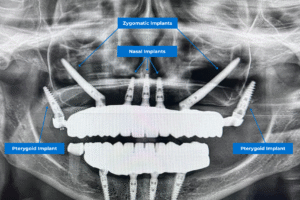

Impianti zigomatici

I pazienti di solito devono affrontare tempi di trattamento più lunghi quando optano per le protesi convenzionali, ma la tecnica del carico immediato riduce drasticamente questi tempi. Ad esempio, il trattamento zigomatico e la tecnica del carico immediato consentono di ottenere una dentizione in meno di ventiquattro ore. Oltre al vantaggio di una maggiore longevità, questa opzione chirurgica consente di evitare un innesto osseo estensivo e di ridurre al minimo i tagli grazie all’utilizzo della tecnica guidata. Tornate a sorridere in 24 ore con gli impianti dentali!

Gli studi scientifici che hanno confrontato il metodo ZAGA con quello tradizionale hanno dimostrato risultati migliori nei pazienti trattati con l’approccio ZAGA rispetto al metodo classico. Infatti, la riabilitazione con impianti zigomatici secondo il metodo ZAGA mostra un tasso di successo superiore al 96% dopo cinque anni. Di conseguenza, il Metodo ZAGA è un insieme specifico di principi e tecniche che si adattano all’anatomia di ciascun paziente. Grazie a questo metodo e all’esperienza dei nostri medici, il paziente riceve una dentatura completa entro 24 ore, con minori complicazioni, tempi di recupero più rapidi, risultati duraturi e, soprattutto, un miglioramento drastico della qualità della vita.